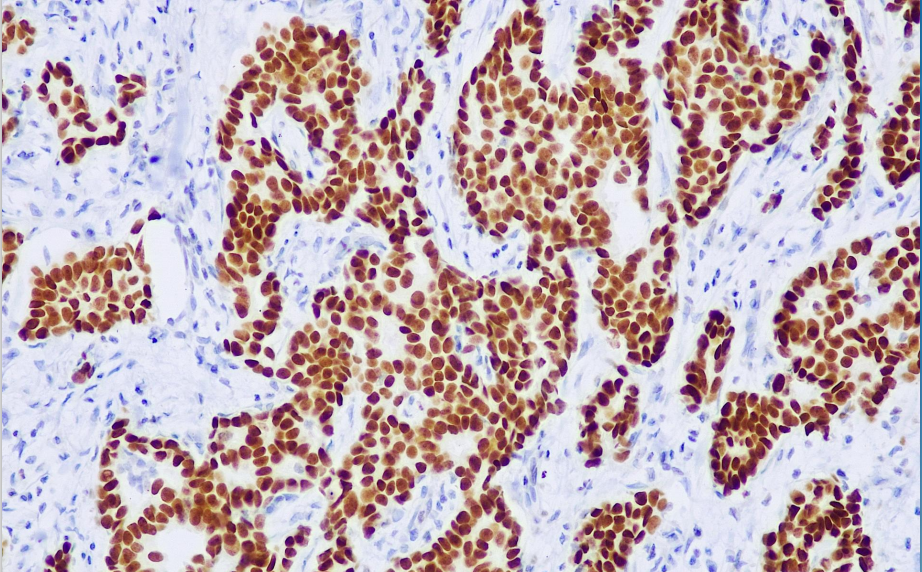

Cellular localization: nucleus

Positive control: Breast cancer/Urinary tract epithelial cancer

GATA3 is a zinc finger transcription factor that participates in the activation, guidance, and regulation of cell proliferation, growth, and differentiation in many tissues. However, in tumor tissues, GATA3 is exclusively expressed primarily in breast cancer and urothelial carcinoma. It has been reported that GATA3 expression in breast cancer is associated with ER, PR, and Her2; in urothelial carcinoma, its expression is positively correlated with tumor invasiveness and grade.

GATA3 antibody reagents can specifically bind to GATA3 molecular antigens. Immunohistochemistry kits containing GATA3 antibody reagents are suitable for the precise diagnosis of breast cancer, urothelial carcinoma, and T-cell lymphoma.